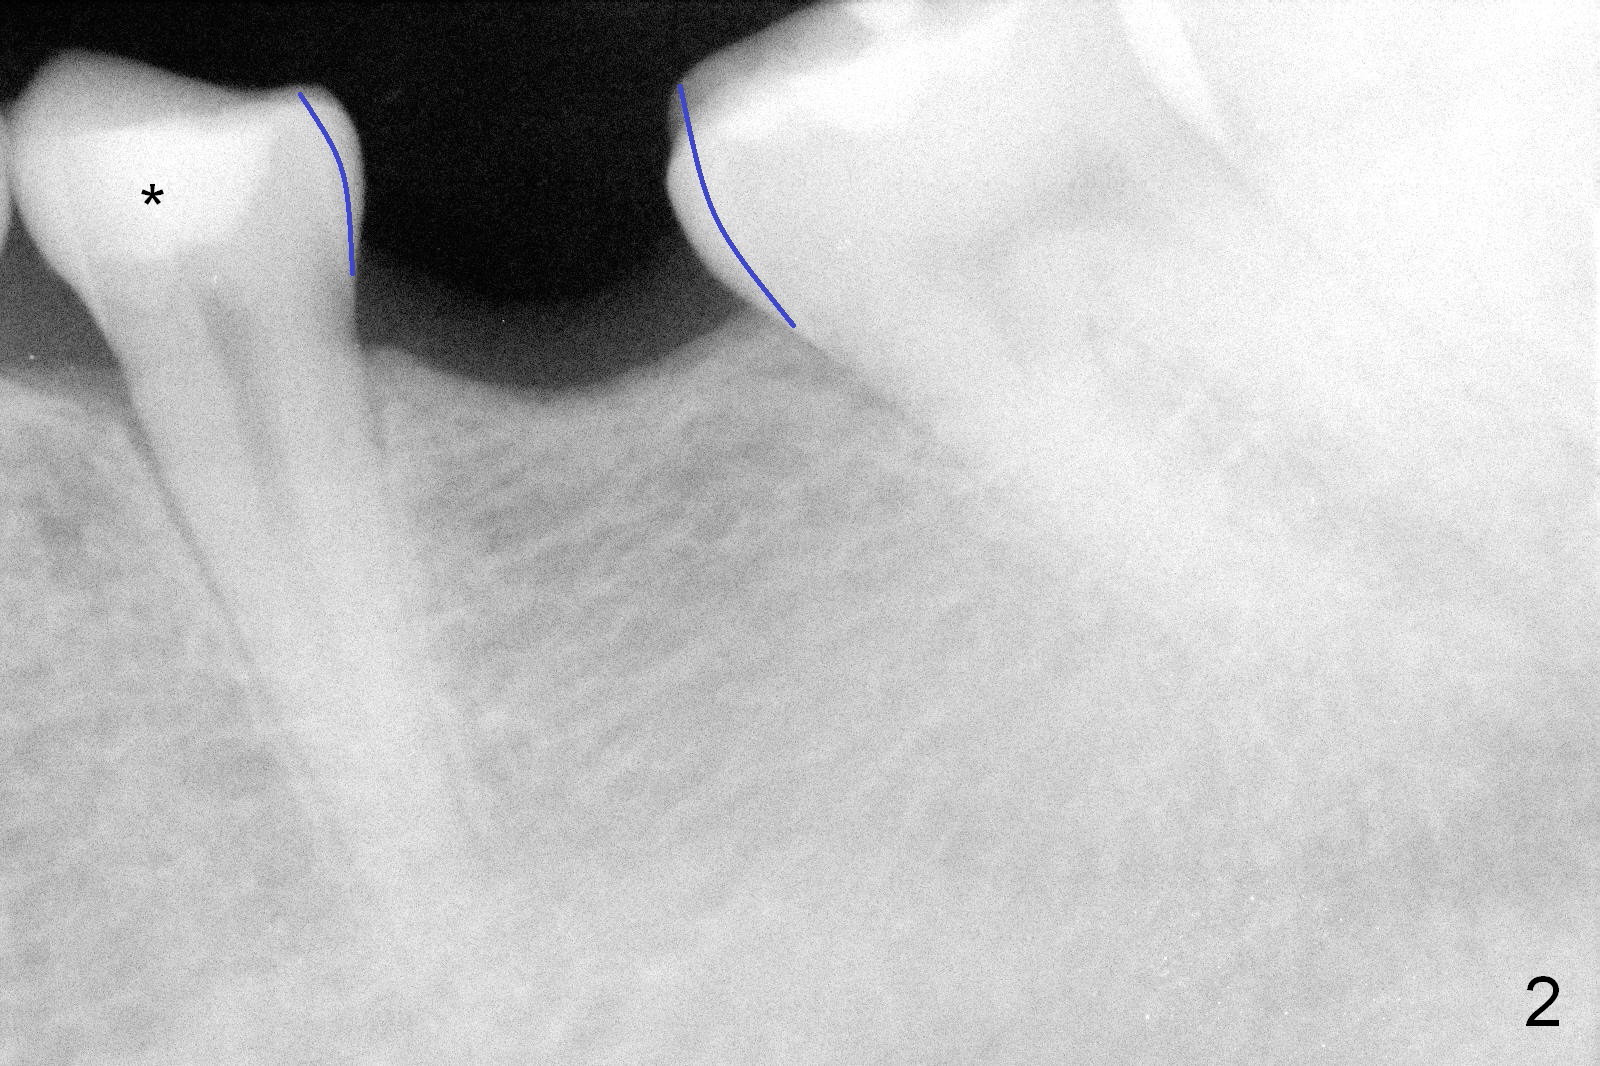

A 31-year-old woman agrees to have implant at #19 (Fig.1) after redoing MOL composite at #20 (Fig.2 *). The edentulous mesiodistal space is narrow (~ 6 mm in Fig.3). If the buccolingual bone width is found to be good after incision, a large implant is preferred. To gain space mesiodistally, the proximal surfaces of the neighboring teeth will be reduced (Fig.2 blue curved lines).

There is no bone loss 3 months postop (Fig.6).